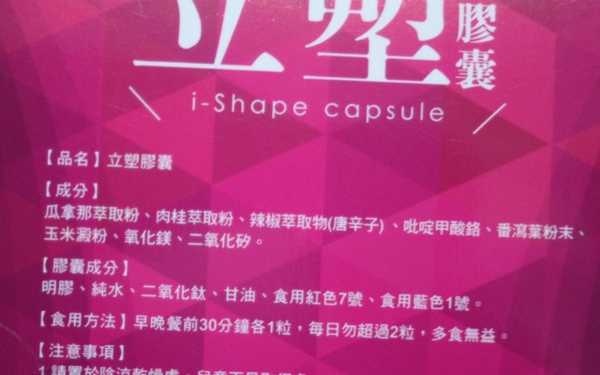

Supercut塑魔纖立塑膠囊的成分有:瓜拿那萃取粉、肉桂萃取粉、辣椒萃取物(唐辛子)、吡啶甲酸鉻、番瀉葉粉末、玉米澱粉、氧化鎂、二氧化矽。

之前上過相關課程,成分表是依照每項成分的多寡來排列順序,排在最前面的就是產品的主要成分!

那我就跟大家分享瓜拿那萃取粉、肉桂萃取粉和辣椒萃取物吧

食用方式:早晚餐前30分鐘各1粒,每日不超過2粒。(多食無益)

番瀉葉萃取物每日食用限量為12mg以下,